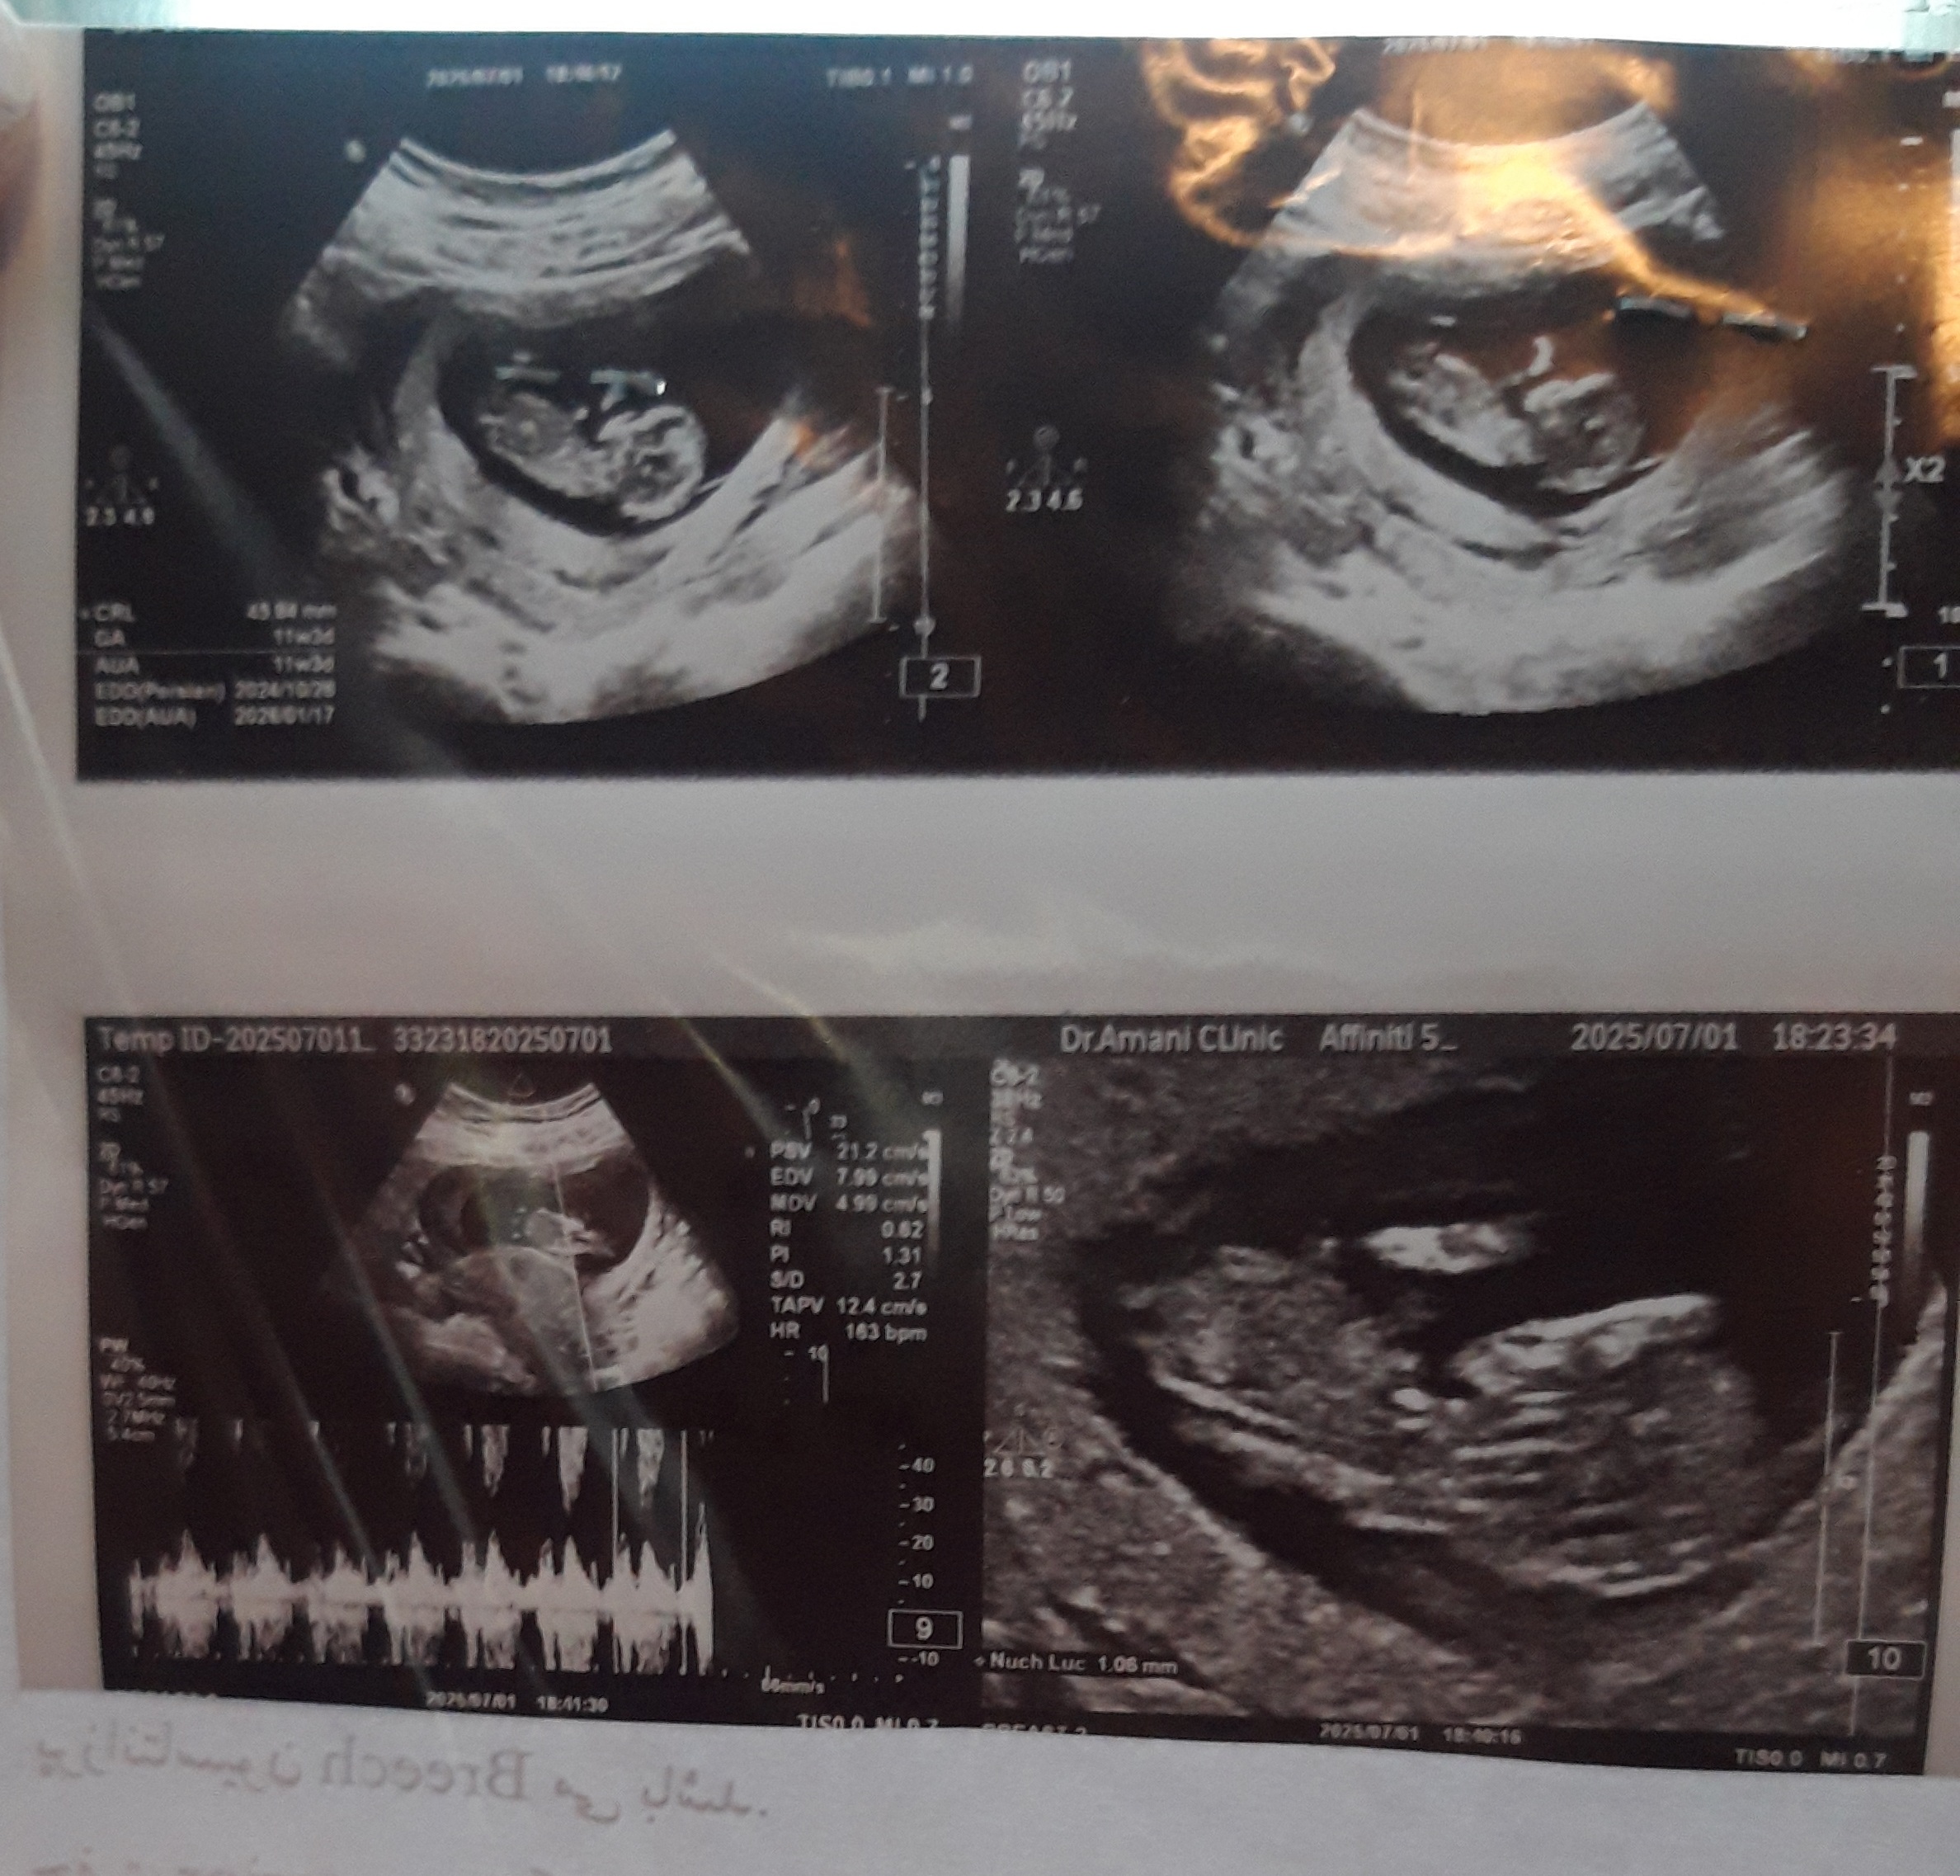

آبانخدخت۲ مدیر استارتر عضویت: 1399/11/12 تعداد پست: 2144 عنوان تعیین جنسیت با عکس سونو 117 بازدید | 17 پست کسی میدونه نی نی من چیه؟؟ فقط 11 هفته و 4 روز به تولد باقی مونده ! 1 5 10 15 20 25 30 35 40 1404/05/12 | 16:57 0 نفر لایک کرده اند ... گزارش تاپیک نامناسب

آبانخدخت۲ مدیر استارتر عضویت: 1399/11/12 تعداد پست: 2144 فقط 11 هفته و 4 روز به تولد باقی مونده ! 1 5 10 15 20 25 30 35 40